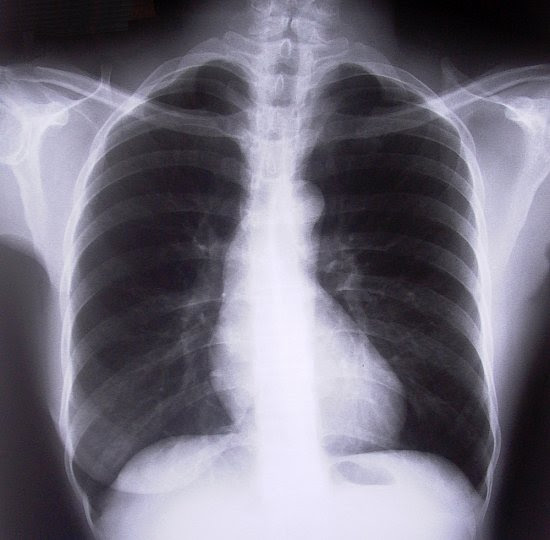

Plicni Embolie Wikiskripta

Plicni Embolie Wikiskripta from www.wikiskripta.eu